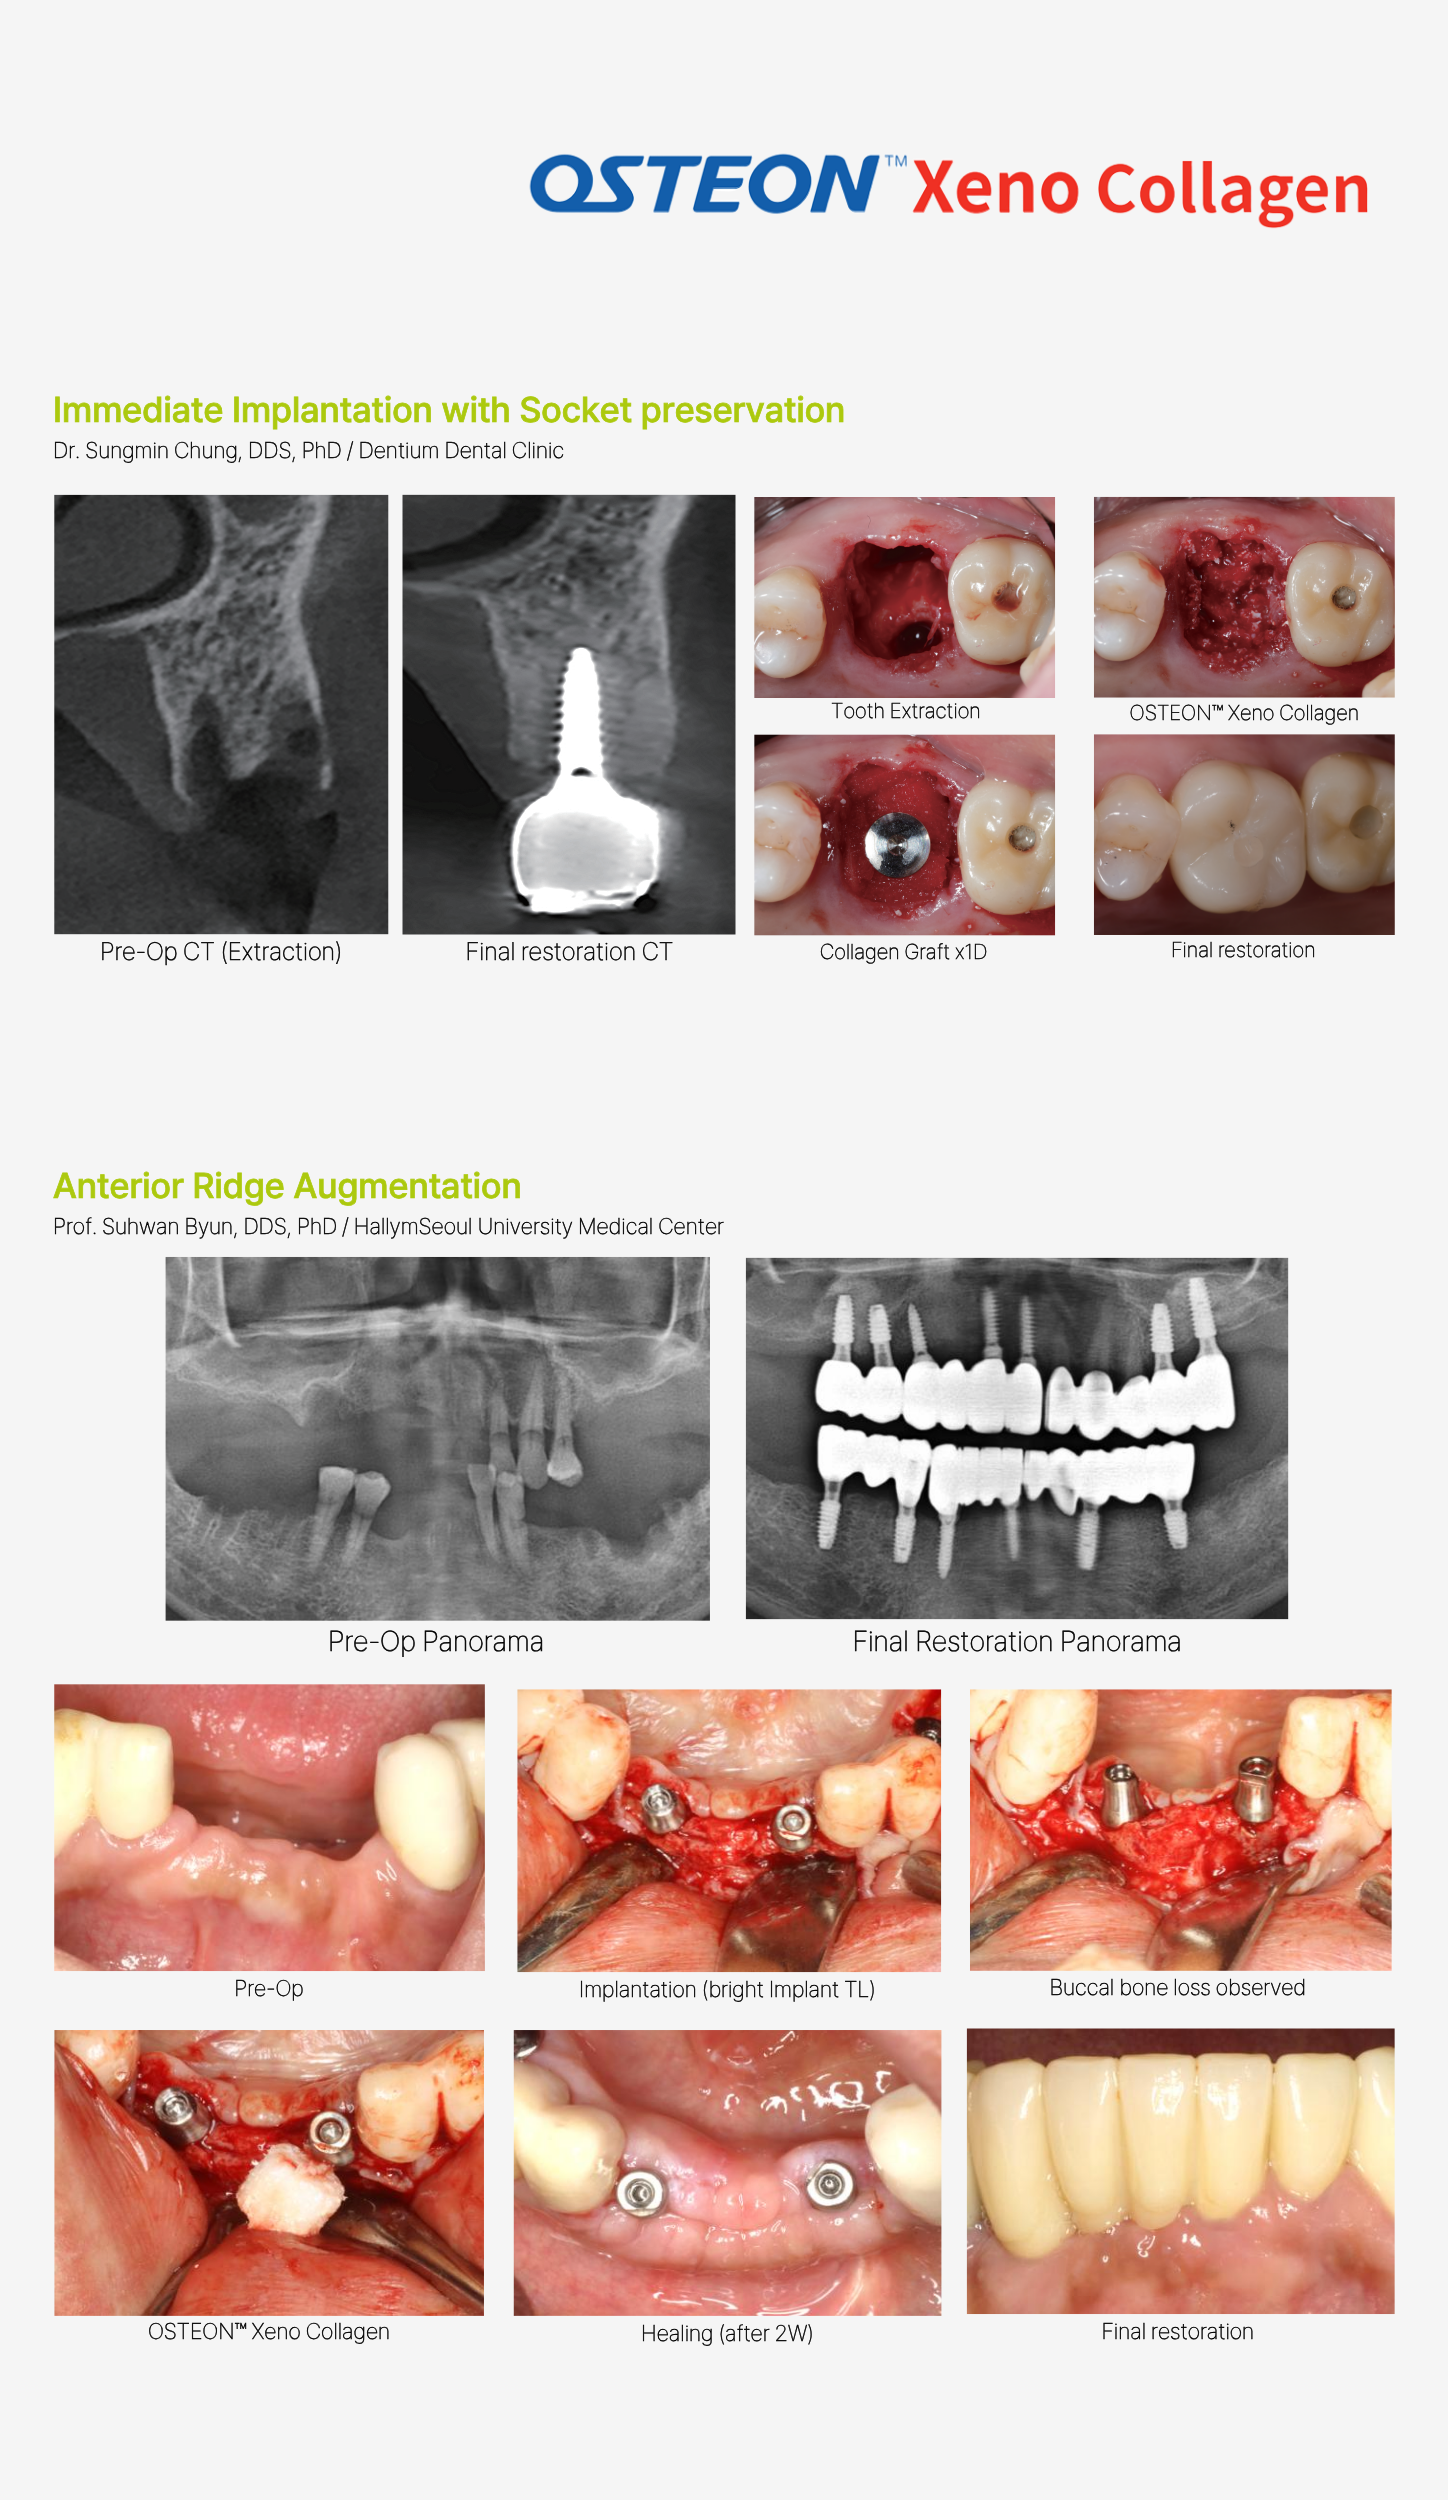

OSTEON™ Xeno Collagen combines the clinically proven, gold-standard advantages of OSTEON™ Xeno granules for Guided Bone Regeneration with collagen-enhanced easy handling, delivering excellent osteoconductive properties, reduced surgery time, and predictable, exceptional clinical outcomes.